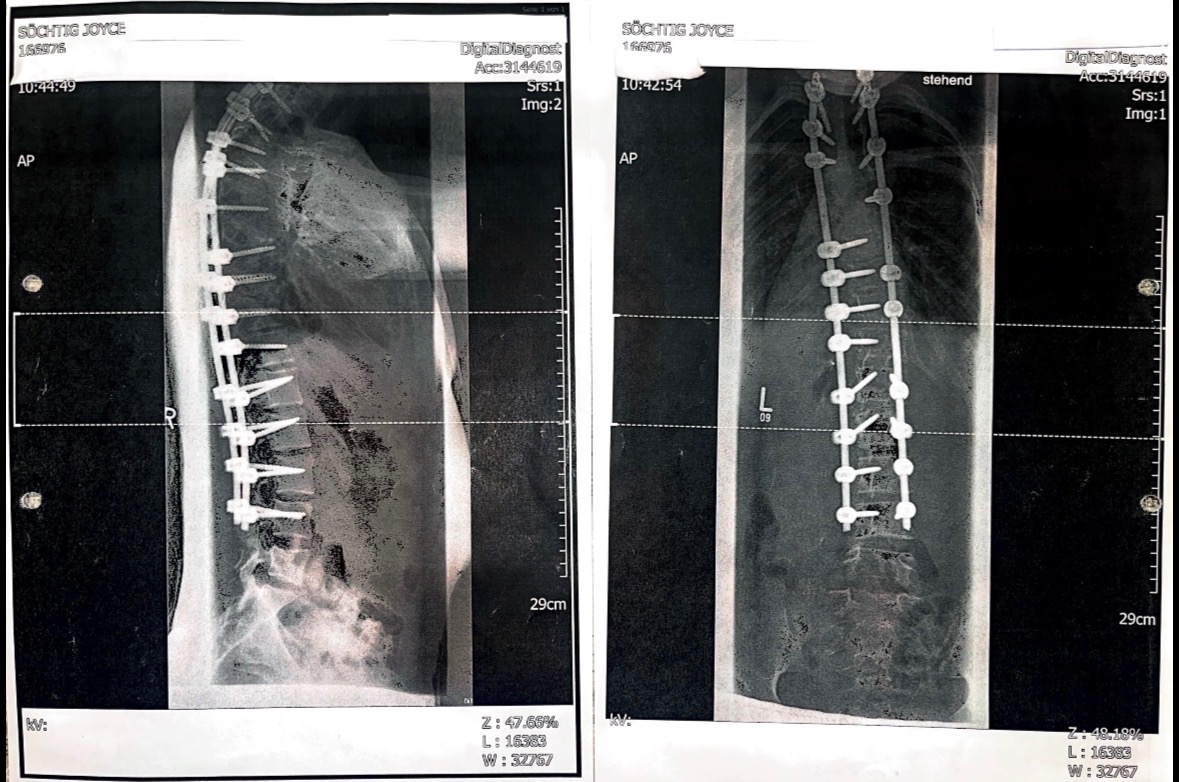

Joyce leidet seit ihrer Geburt an einem schweren Rückenleiden. In ihren erst 19 Lebensjahren musste sie bereits viele Operationen über sich ergehen lassen. Trotz all dieser Eingriffe hat sich ihr Zustand im Laufe der Zeit weiter verschlechtert und zu einer massiven Instabilität der Halswirbelsäule geführt.

Eine spezialisierte Klinik in der Schweiz hat die komplexen Ursachen ihrer Beschwerden erkannt und sieht eine echte Chance, Joyce durch eine erneute Operation ein Leben ohne ständige Schmerzen zu ermöglichen.